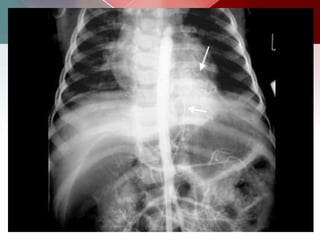

Calcified unilocular hydatid cyst. Contrast material enhanced

CT scan shows a round lesion with water attenuation and a ring like pattern of

calcification (arrows). This pattern represents calcification of the peri-cyst and

strongly suggests a diagnosis of hydatid cyst